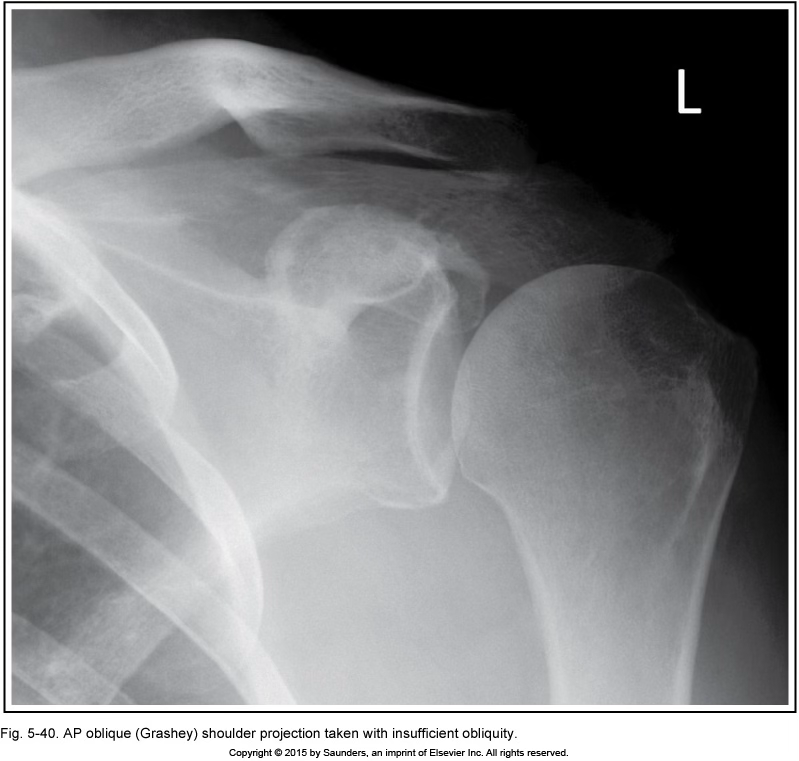

grashey

excessive obliquity

insufficient obliquity